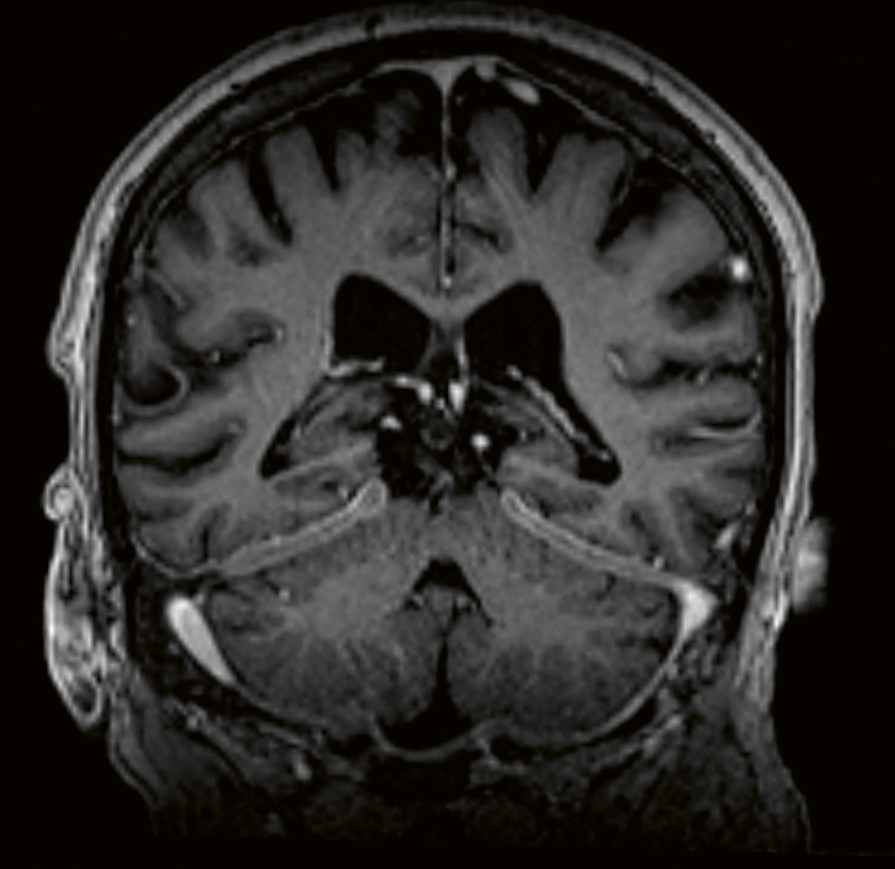

Vid misstanke om neurosarkoidos är det viktigt att utföra en MR-undersökning av hela CNS, det vill säga både hjärnan och ryggmärgen. Dessutom bör MR alltid göras med kontrast. Leptomeningeal uppladdning, både diffus och nodulär i skallbasen, är det vanligaste MR-fyndet (T1-viktad sekvens) vid neurosarkoidos, med en förekomst på 56 procent. Vid spridning till de basala hjärnhinnorna kan man även se påverkan på de lägre kranialnerverna (Figur 1 och 2). Pakymeningit är mindre vanlig som isolerat fynd vid neurosarkoidos (Figur 3) [32, 33]. Kontrastuppladdning i de drabbade kranialnerverna ses ibland vid MR, men inte alltid [34]. MR av hypofysen visar oftast en multi­fokal förstoring och kontrastuppladdning av främre hypofysen och infundibulum, och ibland även av hypo­talamus [35, 36]. Peri­ventrikulära och djupa vitsubstanslesioner, som är högsignalerande på FLAIR- och T2-sekvenser, är vanliga vid neurosarkoidos och kan vara svåra att särskilja från vaskulära förändringar [37]. Hydrocefalus och tumörliknande förändringar förekommer, men är ovanliga fynd vid neurosarkoidos [37]. Vid misstanke om vaskulit bör susceptibilitetsviktad MR-sekvens (SWI), kärlväggs­avbildning och konventionell angiografi utföras. Framträdande medullära vener har beskrivits som ett specifikt fynd vid neurosarkoidos [38].

Figur 2. MR hjärna, T1-viktad, Gd+, som visar meningeal kontrastuppladdning, förtjockad dura bilateralt frontalt höger samt medialt i mellersta skallgropen. Små kontrastladdande noduli längs septum pellucidum.